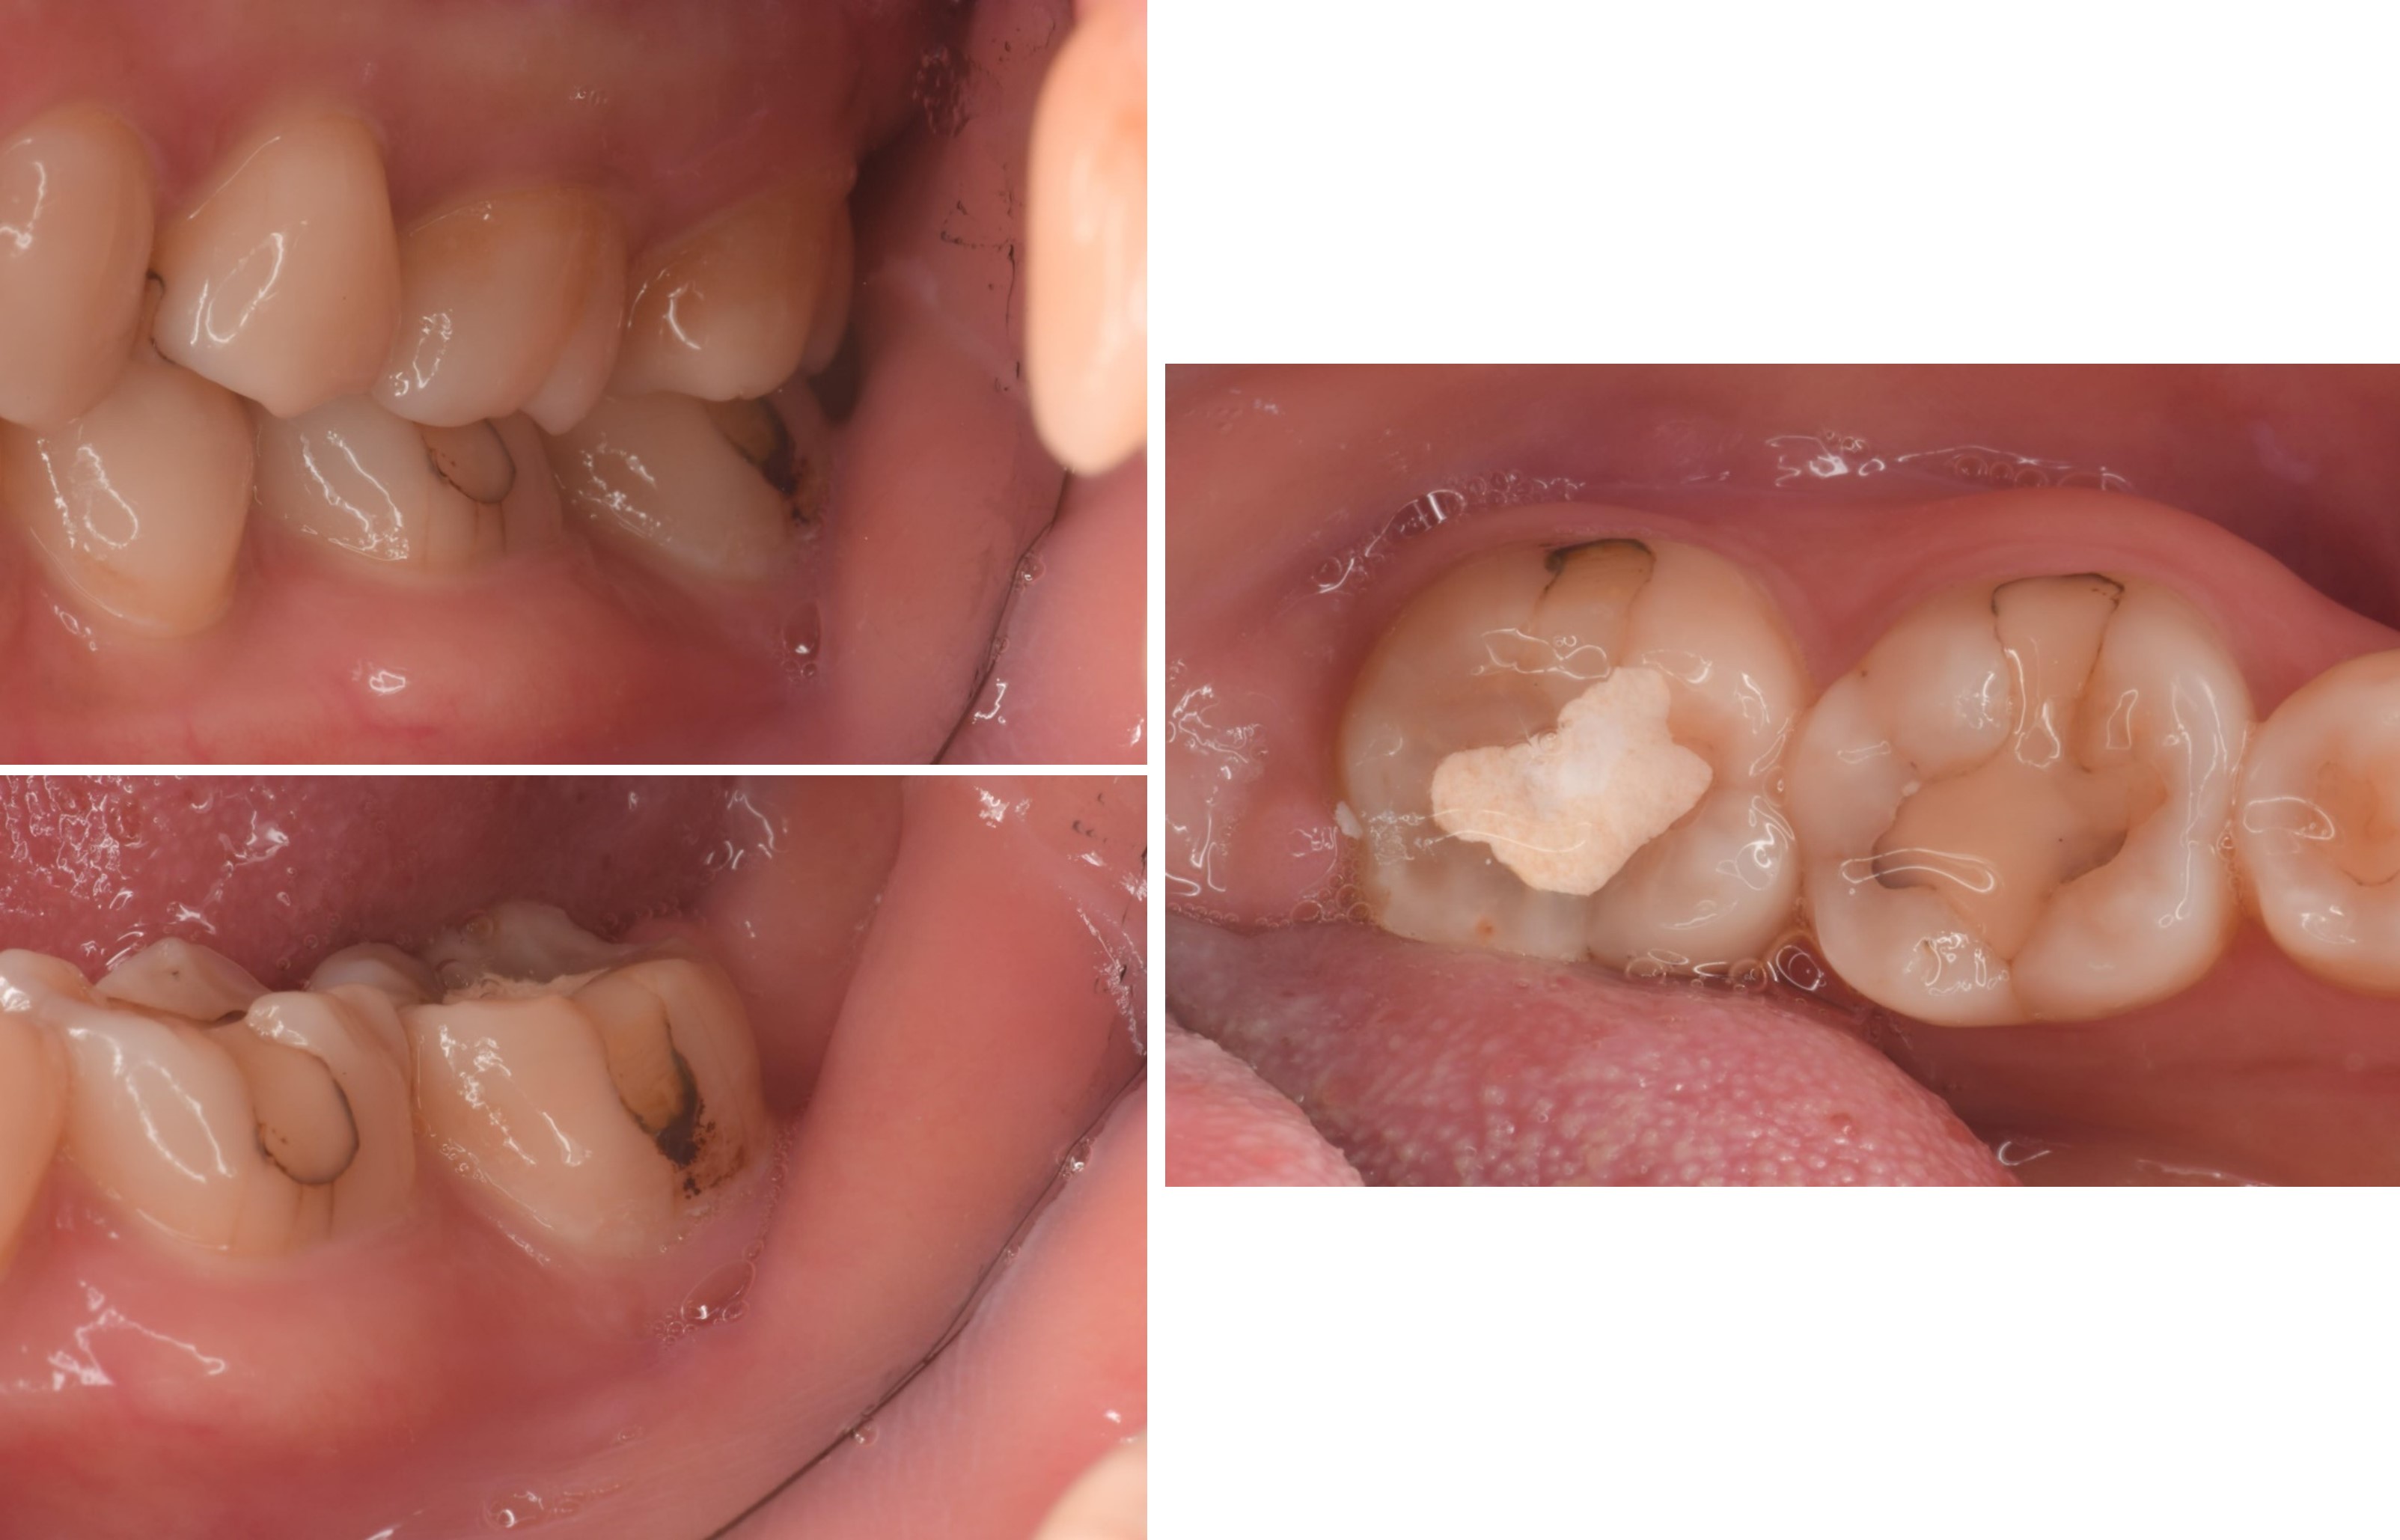

治療前,牙齒蛀牙至牙髓

牙髓受侵犯